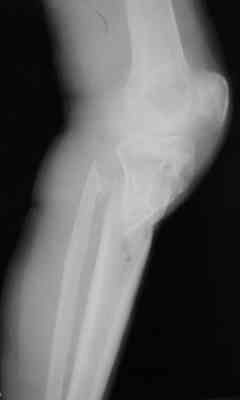

Р-граммы за март и апрель

Р-граммы и фото за 4.05.2007 - 7-е сутки после операции.

Ход операции - линейным разрезом по передней поверхности голени обнажена зона ложного сустава большеберцовой кости. От кости отсепарованы медиально м/ткани. Из зоны ложного сустава убраны рубцовые ткани, мобилизован дистальный отломок. По передней поверхности удалены два осколка, связанных грануляциями. Произведено удаление грануляционной ткани из проксимального отломка (на вид сине-серого цвета), "чистого" гноя не было. Затем произведено наложение аппарата и репозиция отломков. По передне-медиальной поверхности образовался дефект до 4х2х2 см + полость в проксимальном отломке. Удаленные осколки очищены от грануляций, уложены в место дефекта, зажаты между отломками. После иссечения раны по передней поверхности, находящейся рядом с операционной раной, последняя ушита с большим натяжением.

Перелом мыщелка сросся. Проксимальный отломок очень порозный.

На перевязках - из раны небольшое кол-во сукровичного отделяемого. Отек голени умеренный, состояние кожи на фото.

Аппарат видел, репозиции не заметил. О "наложенном" аппарате: спицы в проксимальном отломке б\берцовой кости проведены очень низко, и опять только две, как и в первом аппарате. Почему только одна спица в дистальном парафрактурном кольце? Проксимальная база на бедре должна улучшить стабильность проксимального фрагмента tibia? Ничего подобного двумя спицами в одной базе при таком длинном рычаге вы не добьетесь, а вот совсем потерять движения в коленном суставе они почти гарантируют.

О репозиции: мыщелок сросся и слава Богу, но основные отломки фиксированы в вальгусном положении, собственно как и было, это критично. В чем состояла репозиция?